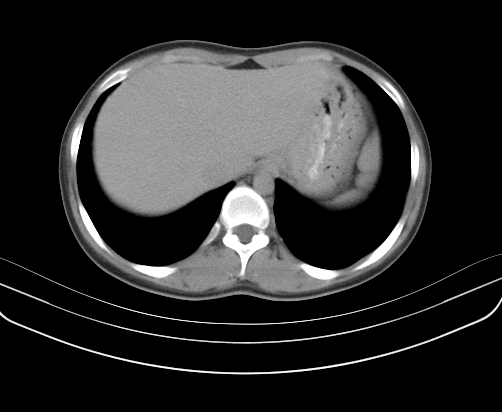

动脉期